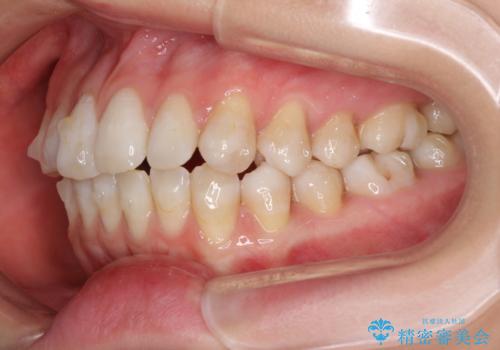

話しにくいオープンバイト インビザラインによる矯正治療

- 前歯の上下スペースによる話しにくさを気にして来院された患者様です。

インビザラインにより上下の前歯の隙間を閉じていくこととしました。

上下の奥歯を圧下させるようにすることで、前歯を接触させるように計画しました。

隙間に舌が入り込むことが話しにくさに繋がっていたため、舌の筋肉のトレーニングも並行して行い、話しにくさの改善と後戻りの抑制を図りました。